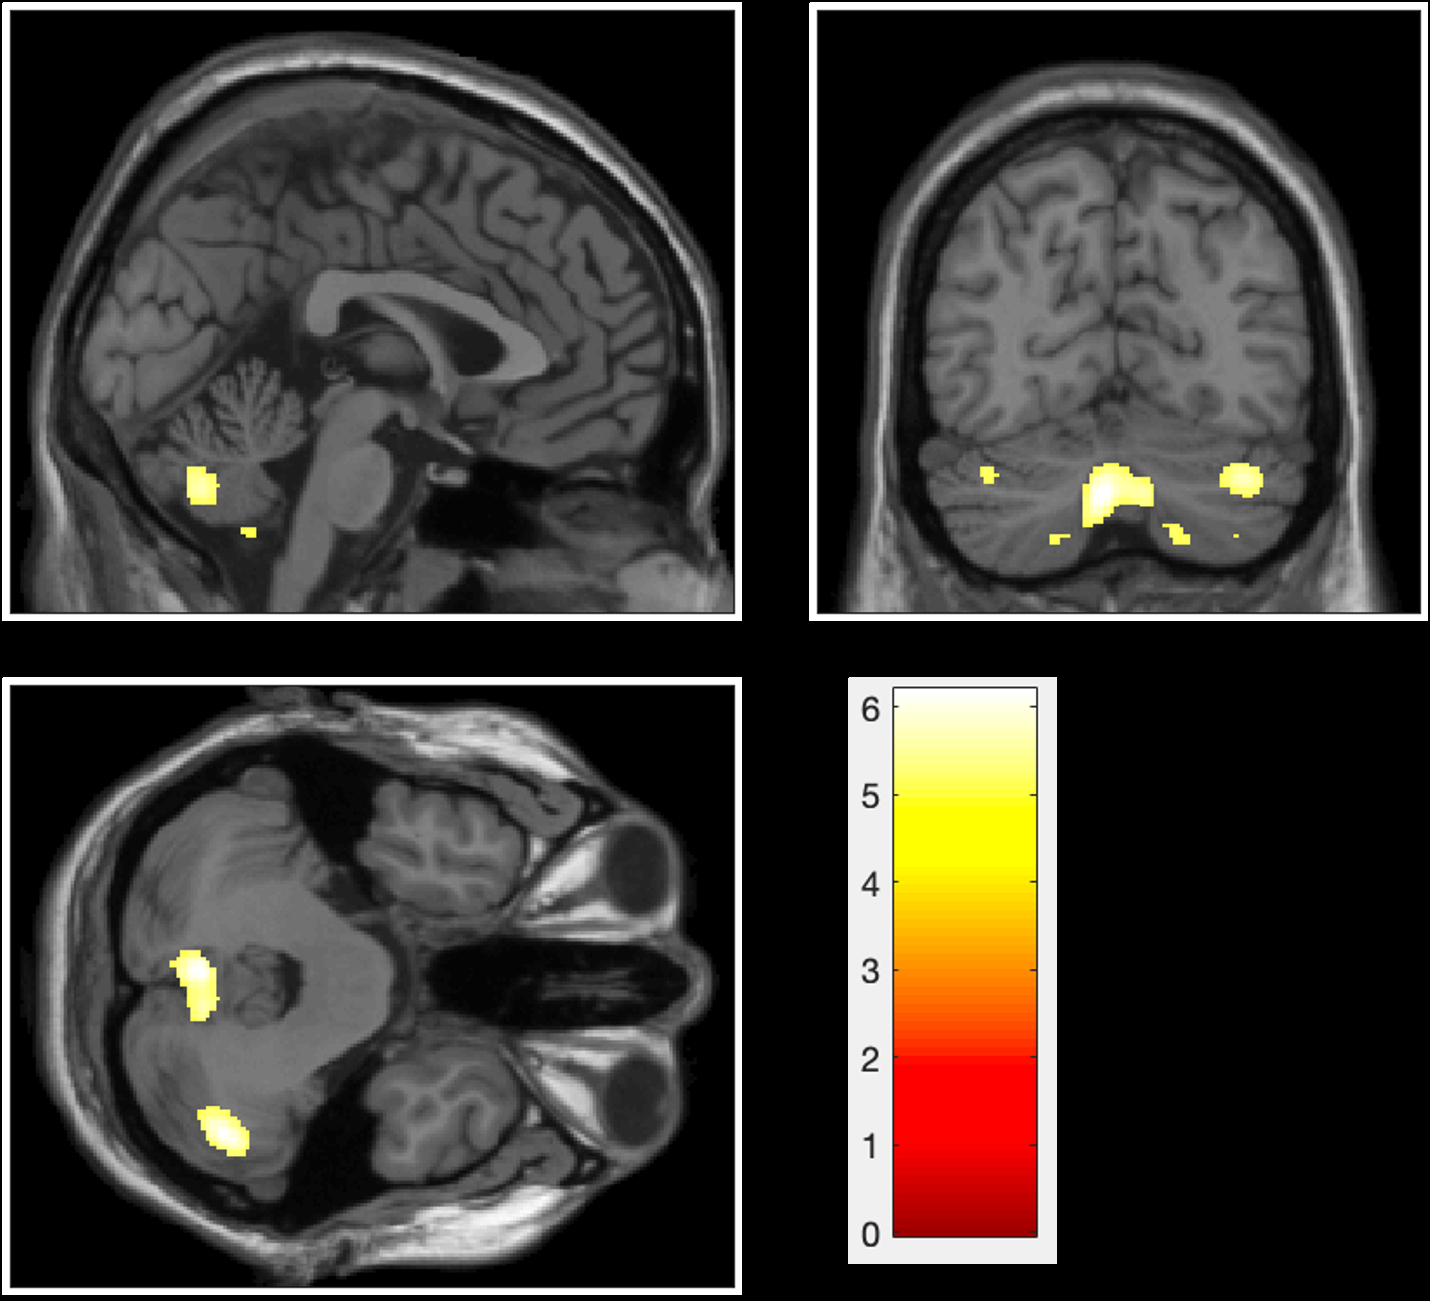

Statistical Parametric Mapping 12 was used to obtain automated, quantitative, voxel-based morphology of cerebral atrophy shown on 5.0T MRI, including total intracranial volume, gray matter volume, white matter volume and cerebrospinal fluid volume. Two-sample t test explores the differences in the spatial distribution characteristics of cerebral atrophy between 36 CAA patients and 51 HTN-CSVD patients. A voxel-wise multiple regression analysis clarifies the correlation between cerebral atrophy and cognitive decline in CAA.

After adjusting for age, gender, and total intracranial volume, cerebral atrophy differences between CAA and HTN-CSVD were mainly observed in the cortex of bilateral cerebellar hemispheres and vermis (p < 0.05 FWE). There is a spatial correlation between cerebral atrophy and cognitive levels in CAA after adjusting for age, gender, and total intracranial volume. Regional brain volume in the left medial temporal lobe, insula, parietal lobe, and thalamus was associated with mini-mental state examination scores (p < 0.05 FDR), and cerebral atrophy in the left lateral temporal lobe and right cerebellar hemisphere was associated with Montreal Cognitive Assessment scores (p < 0.05 FDR).

Cerebral atrophy in CAA is predominantly in the cerebellum, compared to HTN-CSVD, and is independently associated with overall cognitive levels prominantly in left temporal lobe. In conclusion, this study provides valuable reference for a better understanding of the differences of cerebral atrophy between CAA and HTN-CSVD, as well as the clinical relevance of cerebral atrophy.